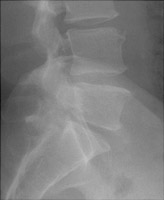

- Click on the image for a larger versionCConed radiograph of the L5-S1 region. The abnormalities are difficult to appreciate.